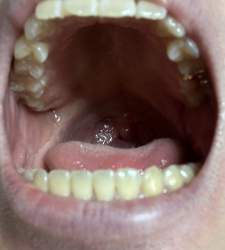

アフター

>アフター

これ歯肉戻るの?

骨も溶けまくってそう

あと歯石があると歯茎の骨が後退して抜けやすくなる

歯肉戻らないんだな

歯肉は毎日歯磨きとかでマッサージしたら戻るそうだ

老人なら知らん